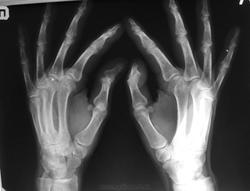

Что за тени указанные стрелками?

Пожилой мужчина пришёл на исследование кистей и стоп. Меня заинтересовали продольные нитевидные тени, указанные красными стрелками. Моё мнение что это склеротические изменения артерий.

Обызвествления стенок сосудов. Сахарным диабетом пациент не болеет?

Значит болеет. Картина характерна для артериосклероза Менкеберга. Хотя (если не подтвердится) артериосклероз может быть и другой этиологии

Артериосклероз Менкеберга (кальцифицирующий склероз средней сосудистой оболочки) развивается у пациентов старше 50 лет. Возрастная дегенерация средней сосудистой оболочки происходит с фокусами кальцификации и даже формированием костной ткани в пределах артериальной стенки. Участки артерии могут стать твердой кальцифицированной трубкой без сужения просвета.

Диагноз обычно становится очевидным при простом рентгенологическом исследовании. Клиническое значение этого заболевания заключается только в том, что артерия не способна реагировать изменением просвета, что приводит к выраженному, но ложному повышению цифр АД при его изменении.